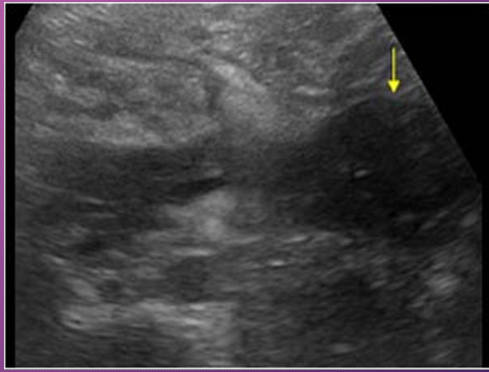

A _______ pancreatitis is an _______ process that spreads along _____ pathways, causing localized areas of diffuse inflammatory _____ of soft tissue that may proceed to necrosis and suppuration

phlegmonous; inflammatory; fascial; edema

______ pancreatitis occurs in ___-___ of patients with _____ pancreatitis

Phlegmonous; 18-20%; acute

Sonographically, phlegmonous tissue appears ______ in texture with good through-_____

hypoechoic; transmission

Sonographically, how does phlegmonous tissue appear?

Hypoechoic with good through transmission

Phlegmonous pancreatitis usually/commonly involves the ____ sac, ____ anterior _____ space, and transverse ______.